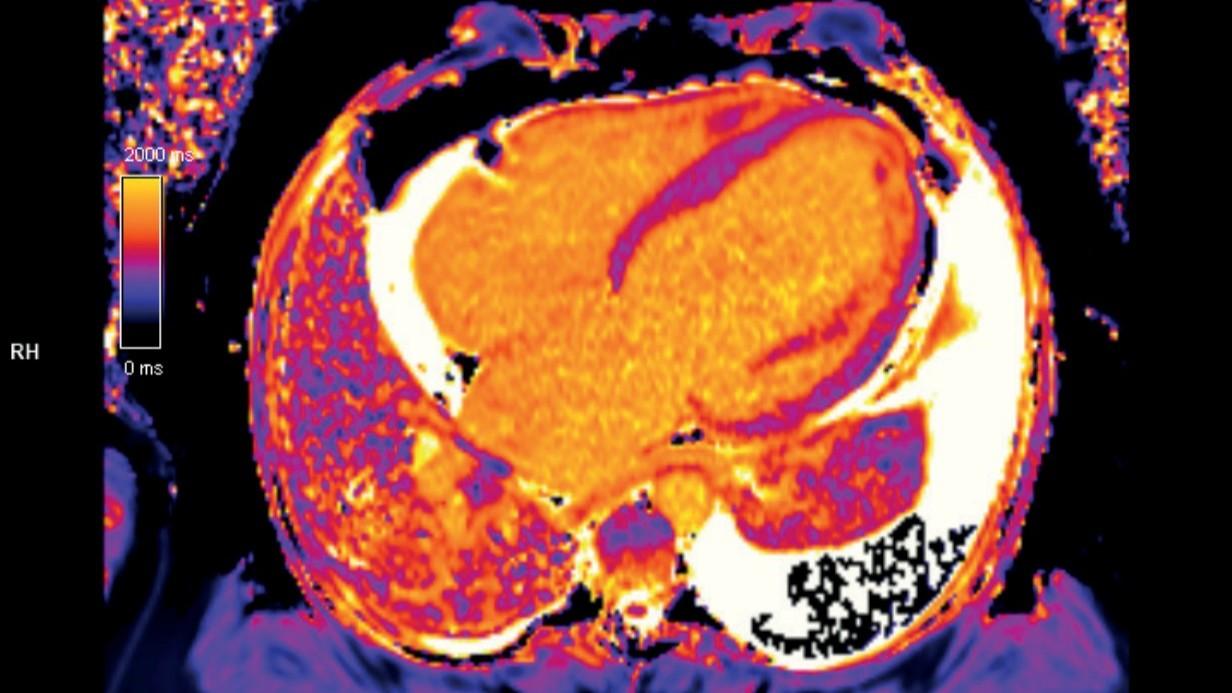

Kardiologiczny rezonans magnetyczny

Data: 23-24 stycznia 2026

Kurs poprowadzą:

- dr n. med. Małgorzata Urbańczyk-Zawadzka

- dr Małgorzata Mielnik

- mgr inż. Paweł Banyś

PROGRAM KURSU

Liczba miejsc jest ograniczona.

Cena: 3 000zł

Kardiologiczny Rezonans Magnetyczny Serca i Naczyń

Data: 14 marca 2026

- dr hab. n. med. Bernadeta Chyrchel

- dr hab. n. med. Karolina Dormiak

- dr n. med. Justyna Rajewska-Tabor

- dr Szymon Rozmarek

Cena 2 000zł